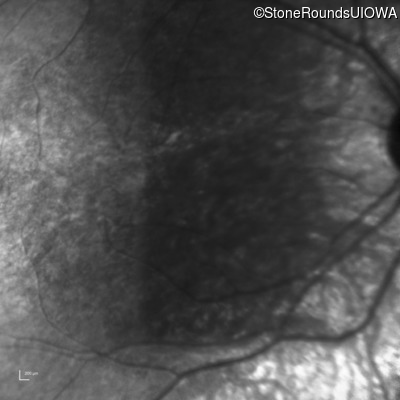

Infrared Fundus Photograph - Right - 5/200

Exemplar